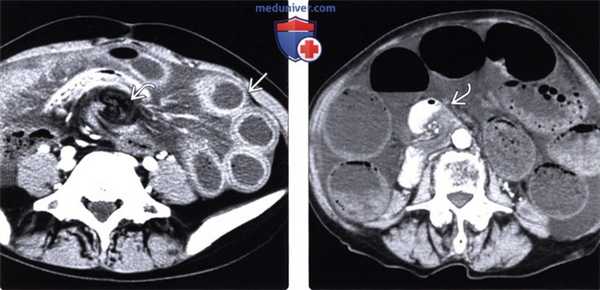

(Слева) На аксиальной КТ с контрастом у пациента с болью в животе после тотальной колэкто-мии (по причине язвенного колита) визуализируется грыжевое выпячивание тонкой кишки через дефект в брыжейке сигмовидной кишки, а также скручивание сосудов брыжейки в области грыжи.

(Справа) На аксиальной КТ с контрастным усилением, выполненной пациенту с выраженной болью и снижением системного давления, определяется признак «водоворота», который заключается в «скручивании» проксимальных отделов тонкой кишки и брыжеечных сосудов вокруг своей оси. При хирургическом вмешательстве было обнаружено грыжевое выпячивание тонкой кишки в дефект брыжейки.